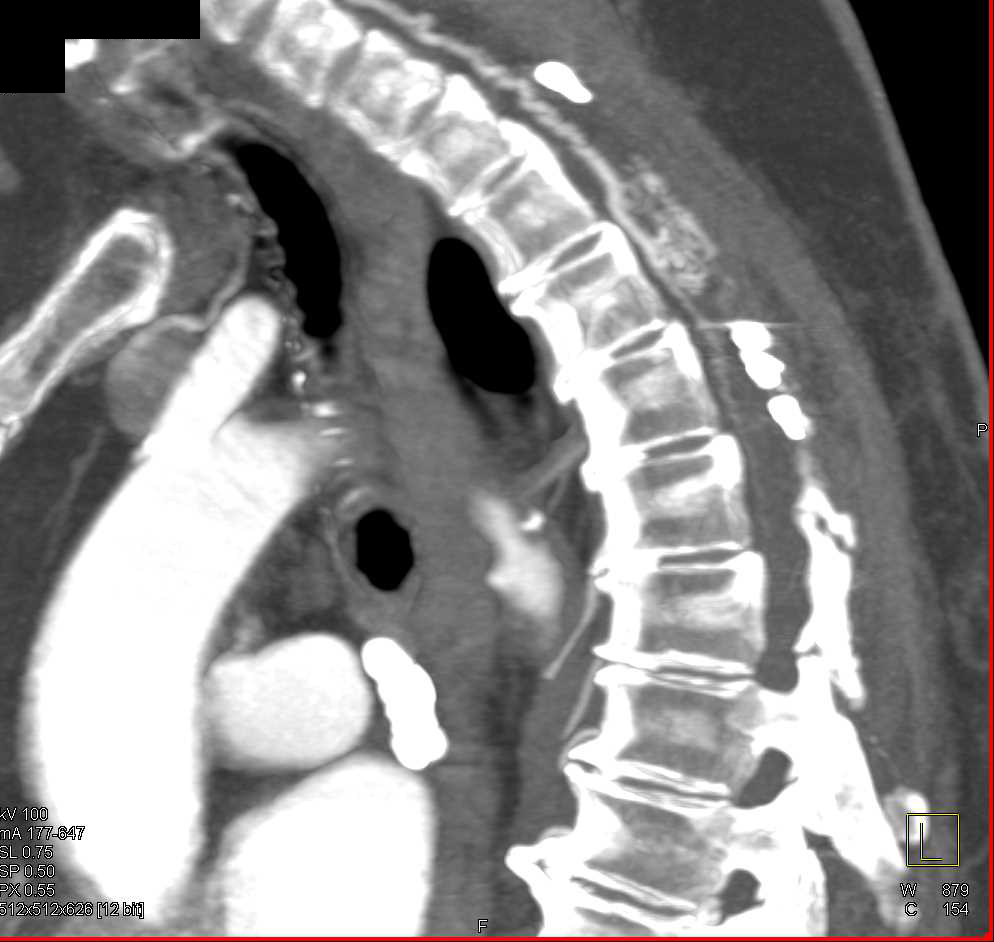

Bicuspid Calcified Aortic Valve with Aortic Stenosis